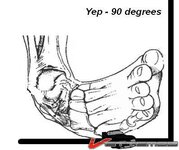

I checked my car - no fire, the other car no fire, but my right foot didn't look so good - 90 degrees to the left - shit that is going to hurt! The wheel was a pretzel.

Right foot was straightened in ER. They said it was dislocated with some small fractures, one from previous idiocy, Soccer [never healed, never will].